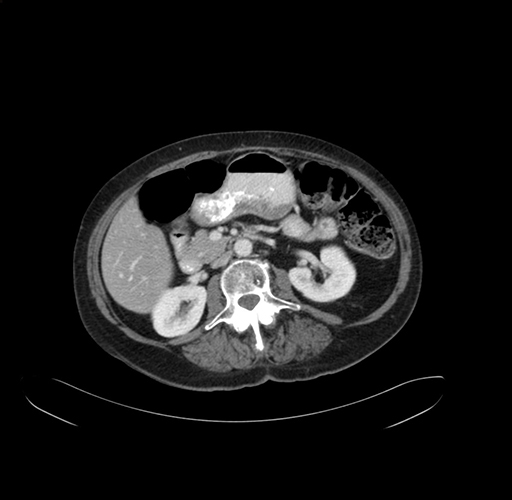

Pre-Chemo: Axial Venous

Axial Venous